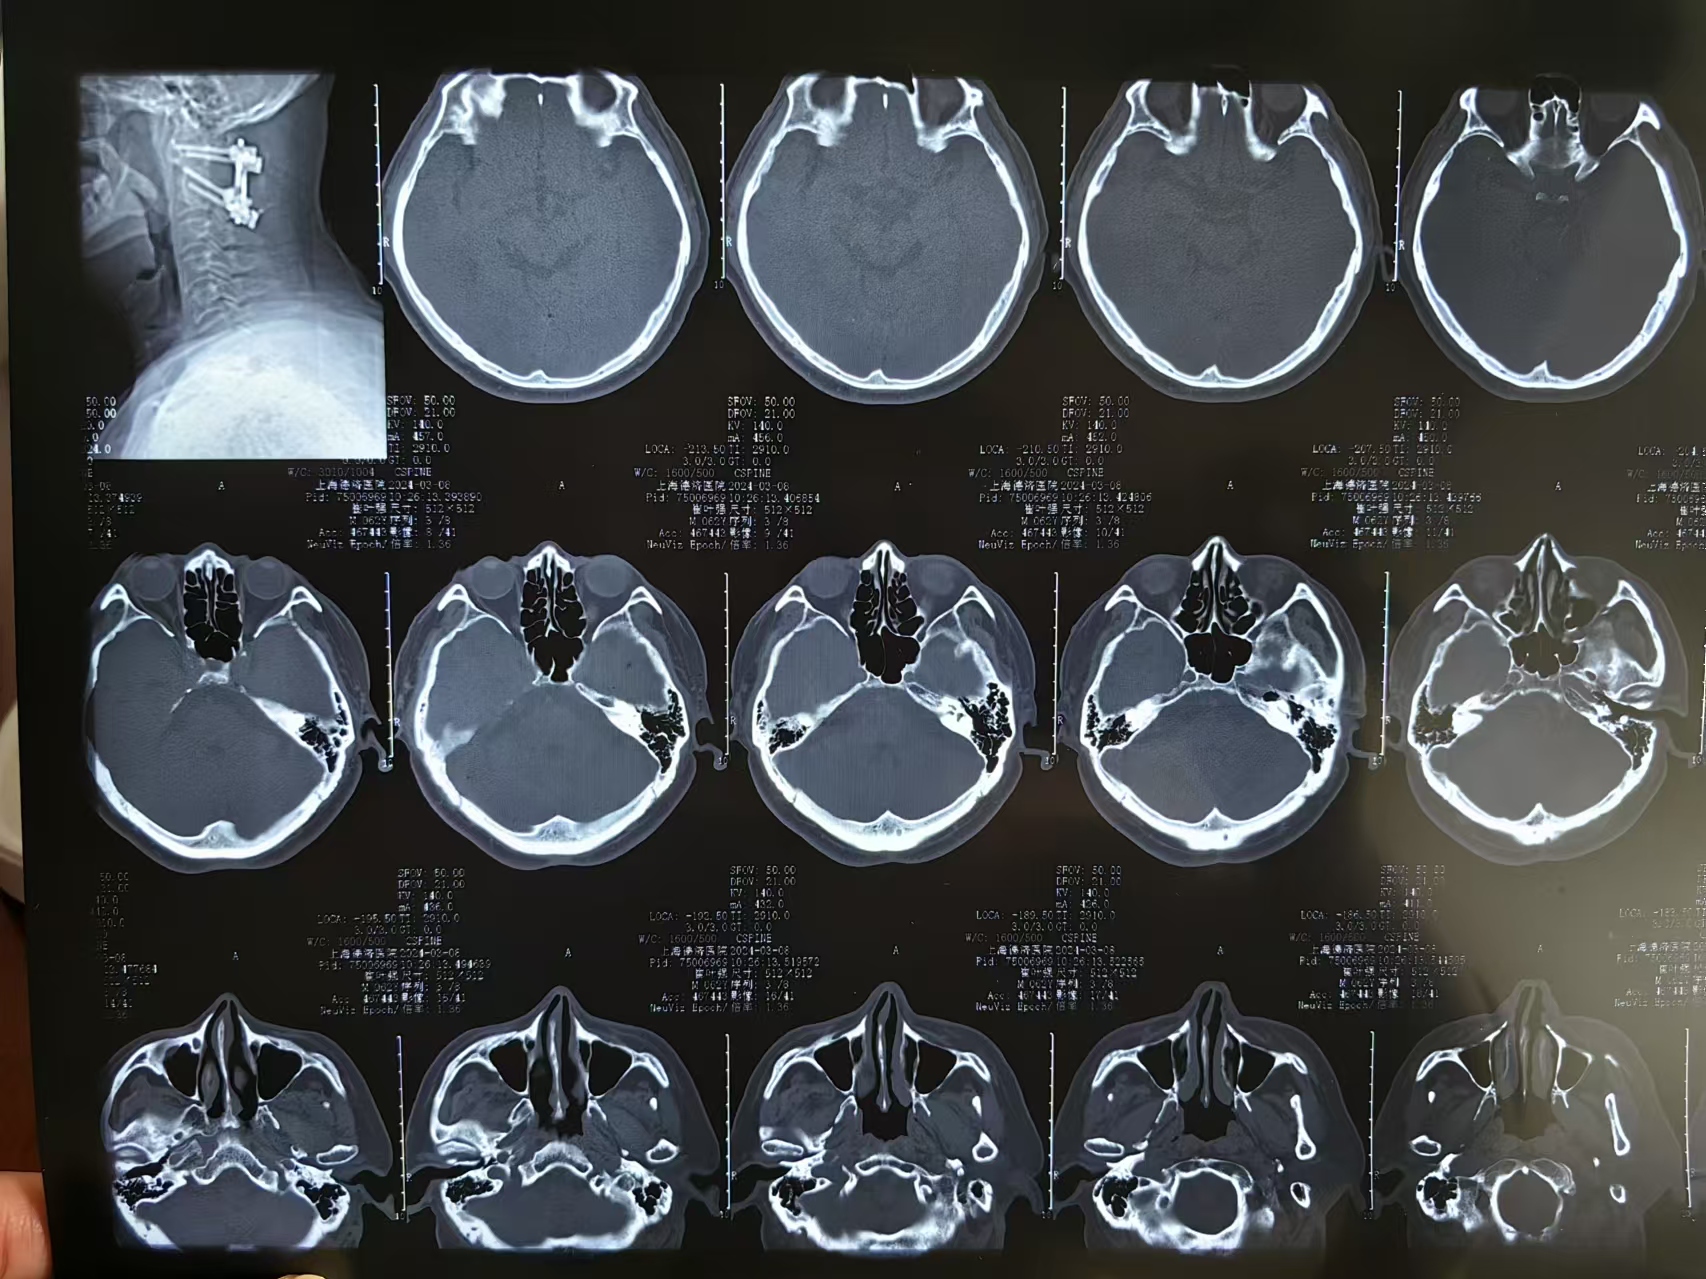

• 诊断:寰枢椎脱位,颅底凹陷

• 影像:

• 术后影像: